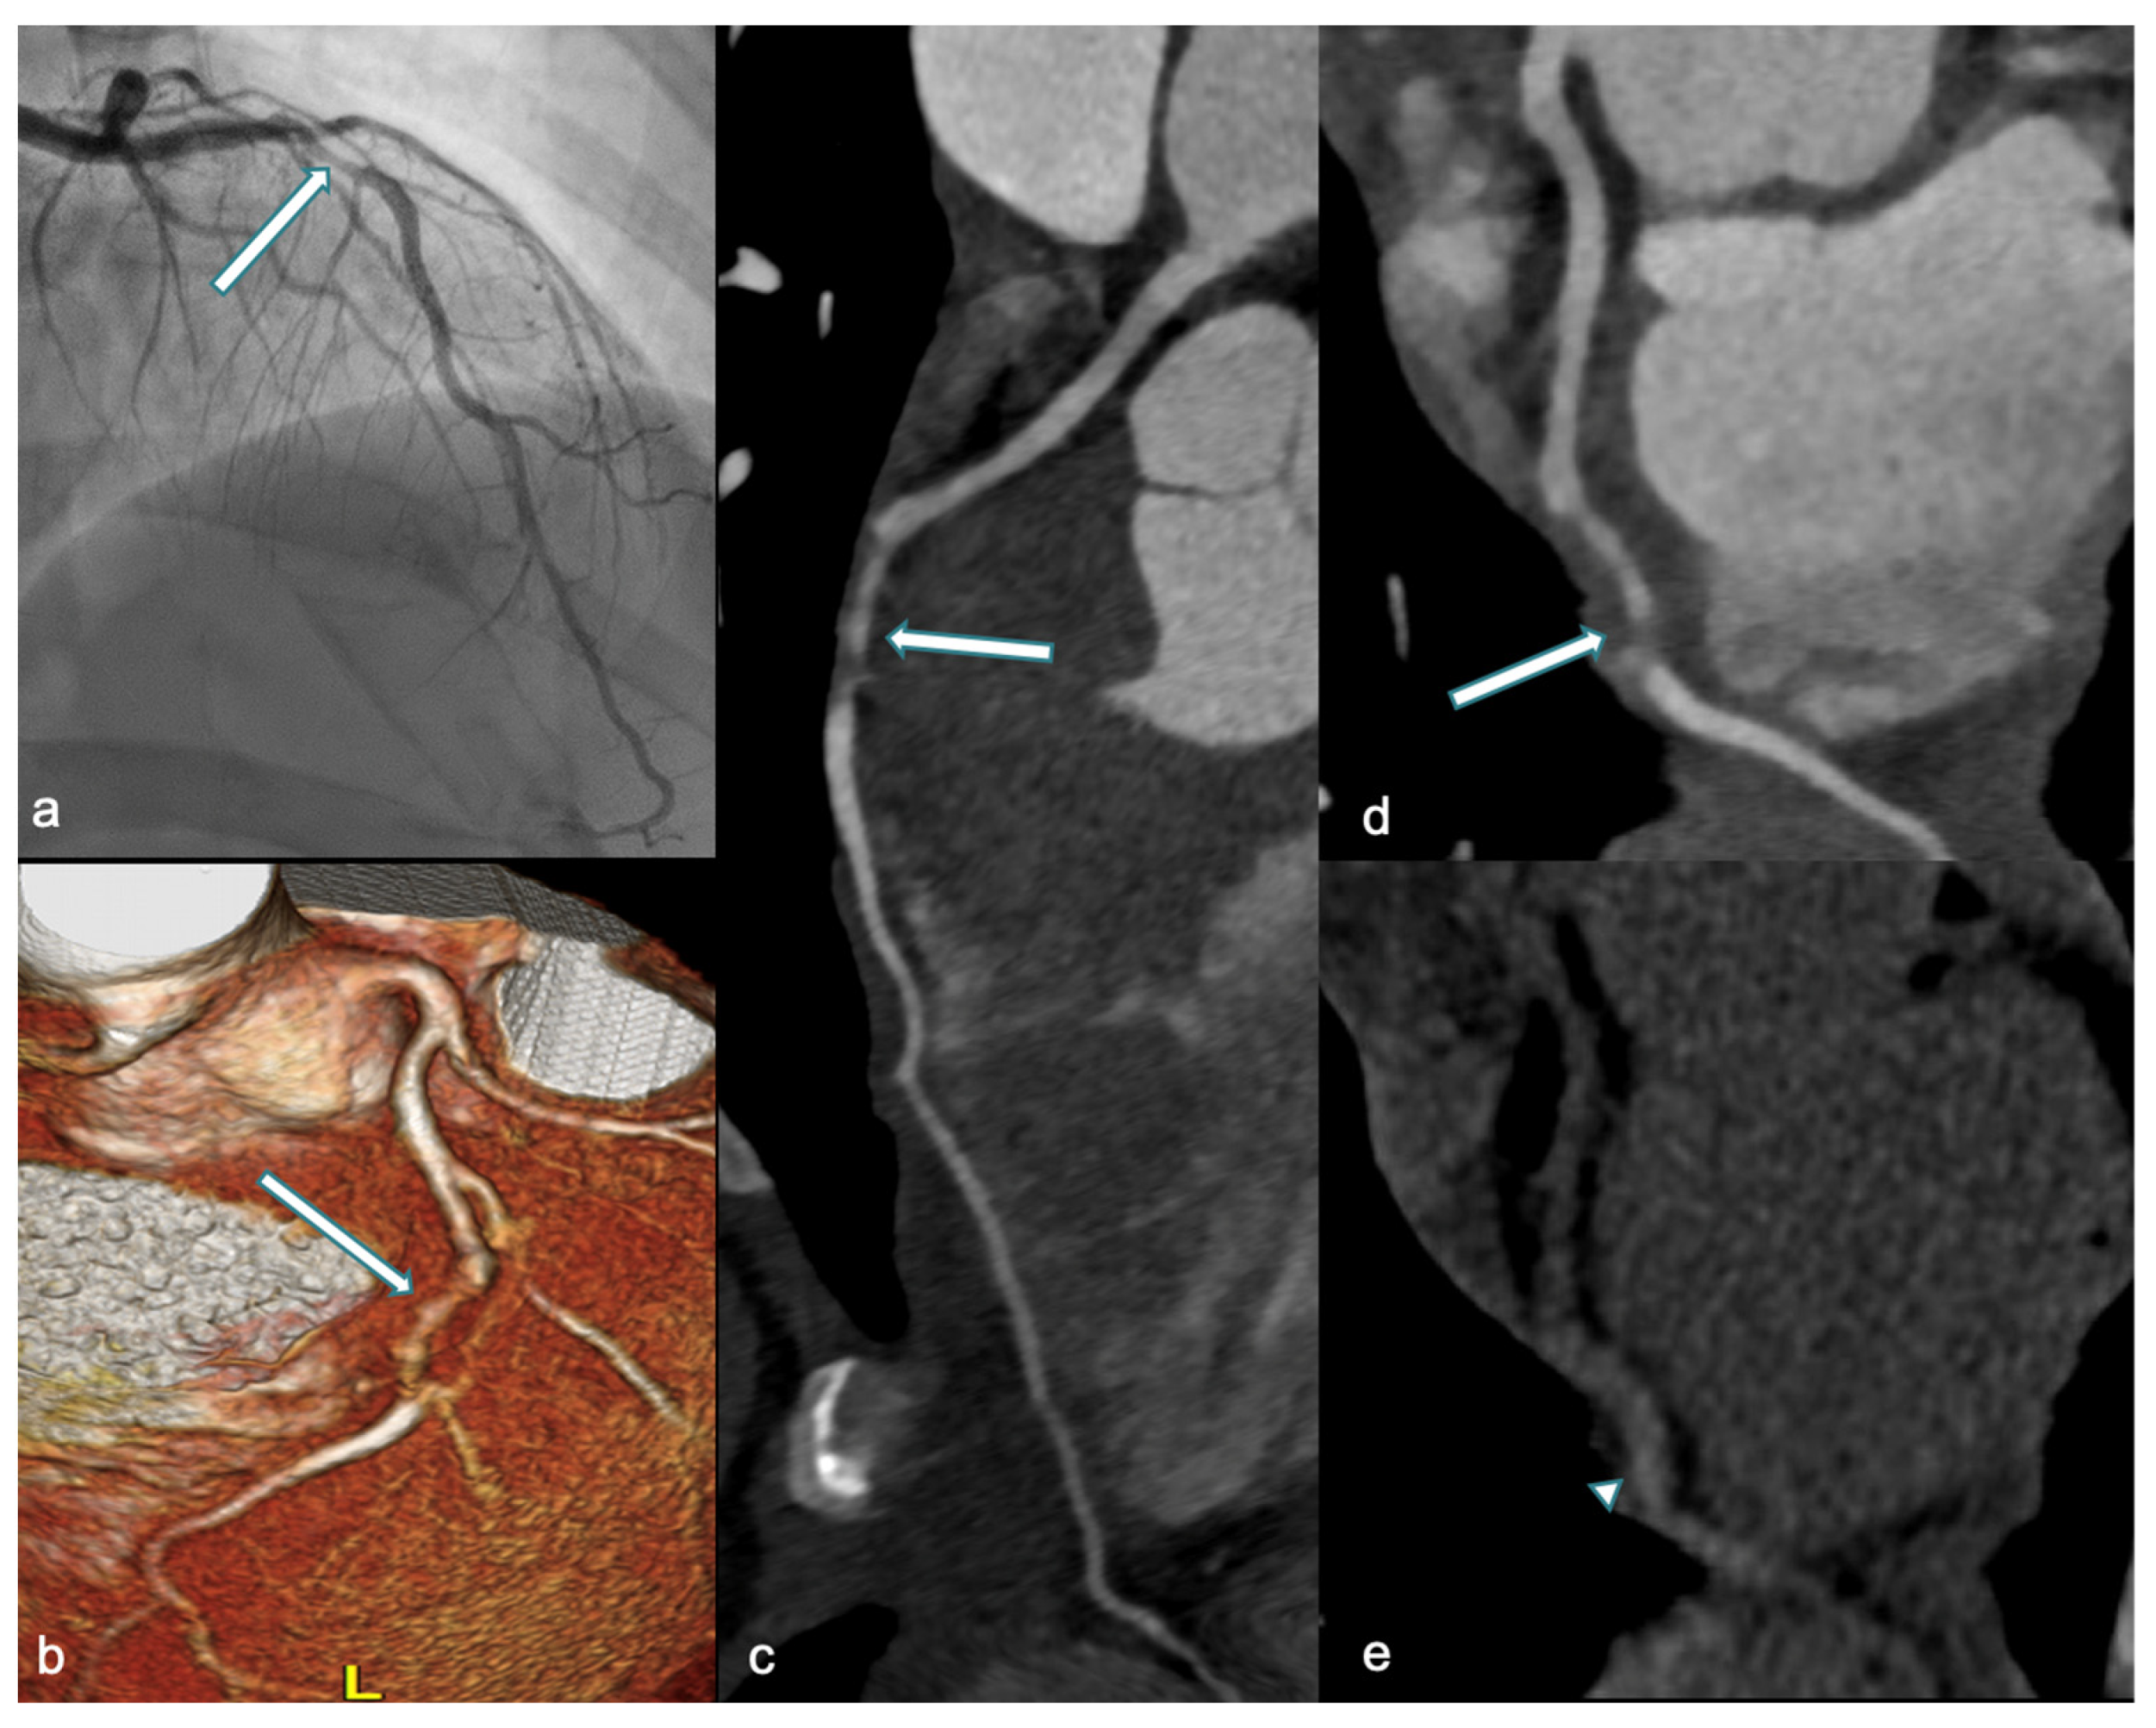

Figure 5.

A 36-year-old woman at week 36 of pregnancy presented with chest pain and anterior ST-segment elevation on ECG. Urgent ICA (a) and CCTA performed one week later (3D-VR, (b) and curved-MPR, (c,d)) revealed a tapered luminal stenosis in the mid-LAD (white arrow), consistent with mid-LAD dissection. In (e), unenhanced CT shows high-density thickening of the mid-LAD wall, suggestive of IMH (arrowhead). ICA: invasive coronary angiography; CCTA: coronary computed tomography angiography; 3D-VR: three-dimensional volume rendering; MPR: multiplanar reconstruction; LAD: left anterior descending artery; and IMH: intramural hematoma.